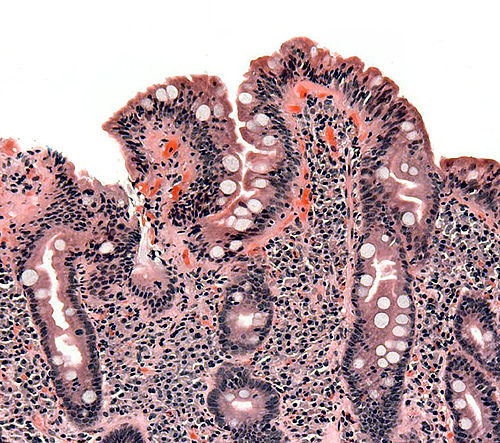

Κοιλιοκάκη: Συμπτώματα, Διάγνωση και Σύγχρονη Αντιμετώπιση

Η κοιλιοκάκη είναι ένα χρόνιο αυτοάνοσο νόσημα που προκαλείται από την ανοσολογική αντίδραση του οργανισμού στη γλουτένη. Η κατανάλωση γλουτένης προκαλεί φλεγμονή και βλάβη στο λεπτό έντερο, επιδρώντας στην απορρόφηση θρεπτικών συστατικών και επηρεάζοντας ολόκληρο τον οργανισμό. Τι είναι η Κοιλιοκάκη; Η κοιλιοκάκη είναι μια πάθηση κατά την οποία το ανοσοποιητικό σύστημα επιτίθεται στις εντερικές…